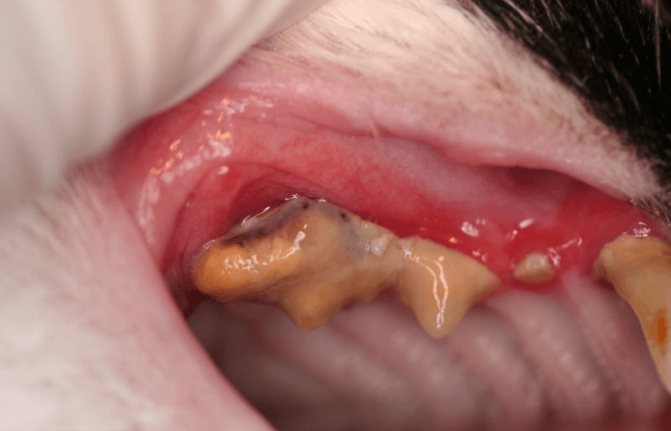

Гингивит

Гингивит — это воспаление дёсен, один из симптомов парадонтоза. Проявляется как покраснение дёсен вокруг зубов. Очень часто гингивит поражает не только дёсны, но и костные ткани.

гингивит — это воспалительное забоолевание дёсен

Лечение гингивита производится специальными препаратами. Во время лечения обязательно кормить кошку только мягкой пюреобразной пищей и проводить ежедневную гигиену полости рта.